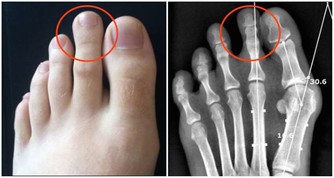

公孫穴屬足脾經經脈的穴道,位於人體足內側緣,在腳中拇趾後大約2寸左右的地方(見下圖),沿著腳拇指後的腳掌骨按壓,什麼時候有酸脹或是酸痛的感覺就證明找對地方了。與脾胃有關的問題,都有很好的調治效果。

▲公孫穴